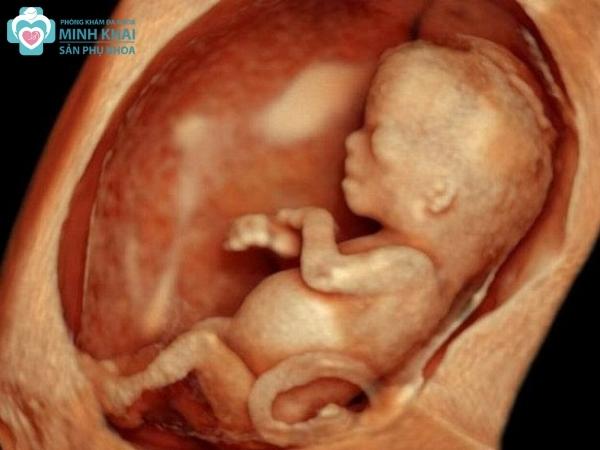

Hình ảnh siêu âm 3D thai nhi tuần 12-15

Trong 3 tháng đầu thai kỳ, hình ảnh phôi thai được phương pháp siêu âm 3D thể hiện sinh động và rõ nét trong bức ảnh. Đây là khoảng thời gian em bé hiếu động nhất nên các bức ảnh 3 chiều có thể phản ánh được hoạt động của thai nhi như ngáp, dụi mắt, nắm tay,...khá rõ ràng. Ngoài ra, nó còn cho mẹ xác định vị trí mắt, mũi và miệng trên gương mặt bé nhưng chưa thể soi được cụ thể bố cục, đường nét khuôn mặt chi tiết theo từng bộ phận.